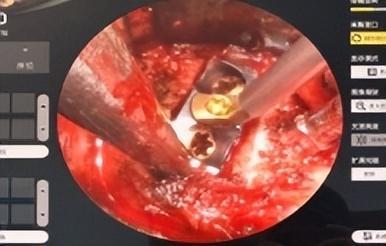

经过充分讨论及术前准备,予以行新型微创通道软镜系统颈椎前路椎间盘切除减压椎间融合术(Anterior cervical discectomy and fusion,ACDF),术中出血10毫升,术后复苏后患者右上肢疼痛即消失,手术效果立竿见影。

▲术中微创通道软镜系统应用

新型微创通道软镜系统ACDF手术是一项新兴的颈椎微创手术,它整合内镜放大系统,便于术者、助手及手术参观者观察手术术野,并可促进教学,适用于神经根型颈椎病和脊髓型颈椎病,与传统开放式颈椎前路手术比较,该术式还具有诸多优点:

2.视野更清晰,可以提供光源、术区放大,可清晰的看到椎间盘、钩椎关节、后纵韧带、硬膜囊,进行精准减压,手术效果更好,有效降低脊髓和神经损伤几率;